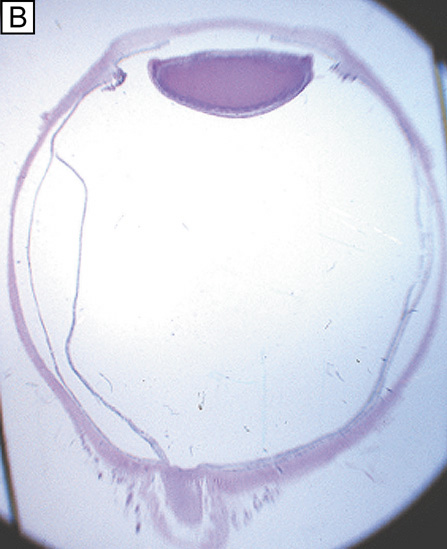

When viewed anteriorly in the living eye, the adult human cornea is somewhat elliptical; the largest measurement is typically in the horizontal meridian (mean 11.7 mm) and the smallest is in the vertical meridian (mean 10.6 mm). The elliptical configuration is brought about by an anterior extension of the opaque scleral structure superiorly and inferiorly. When viewed from the posterior surface of the dissected eye, the cornea is circular, with an average horizontal and vertical measurement of 11.7 mm. The average radius of curvature of the anterior corneal surface is 7.8 mm, which is significantly less than the 11.5 mm average radius of curvature of the sclera. This results in a small, 1.5- to 2-mm wide transition zone that forms an external and internal surface groove, or scleral sulci, where the steeper cornea meets that of the flatter sclera. These sulcus typically are not as obvious to see clinically because they are filled in by overlying episclera and conjuctiva or trabecular meshwork.

The tissue in this transition zone is known as the limbus and is important because it is used as surgical landmark for various anterior segment surgeries, contains corneal epithelial stem cells, contains the conventional outflow pathway for the aqueous humor, is the inciting site of pathology in a few immunologic or cancerous diseases, and possibly contains stem-like corneal endothelial cells (Fig. 2). The limbus is a definite anatomic landmark, or geographical reference, used for planning surgical entry into the anterior segment because it appears clinically as a blue transition zone. Therefore, an incision placed anterior to blue zone is anatomically in the peripheral cornea, safely inside the trabecular meshwork.